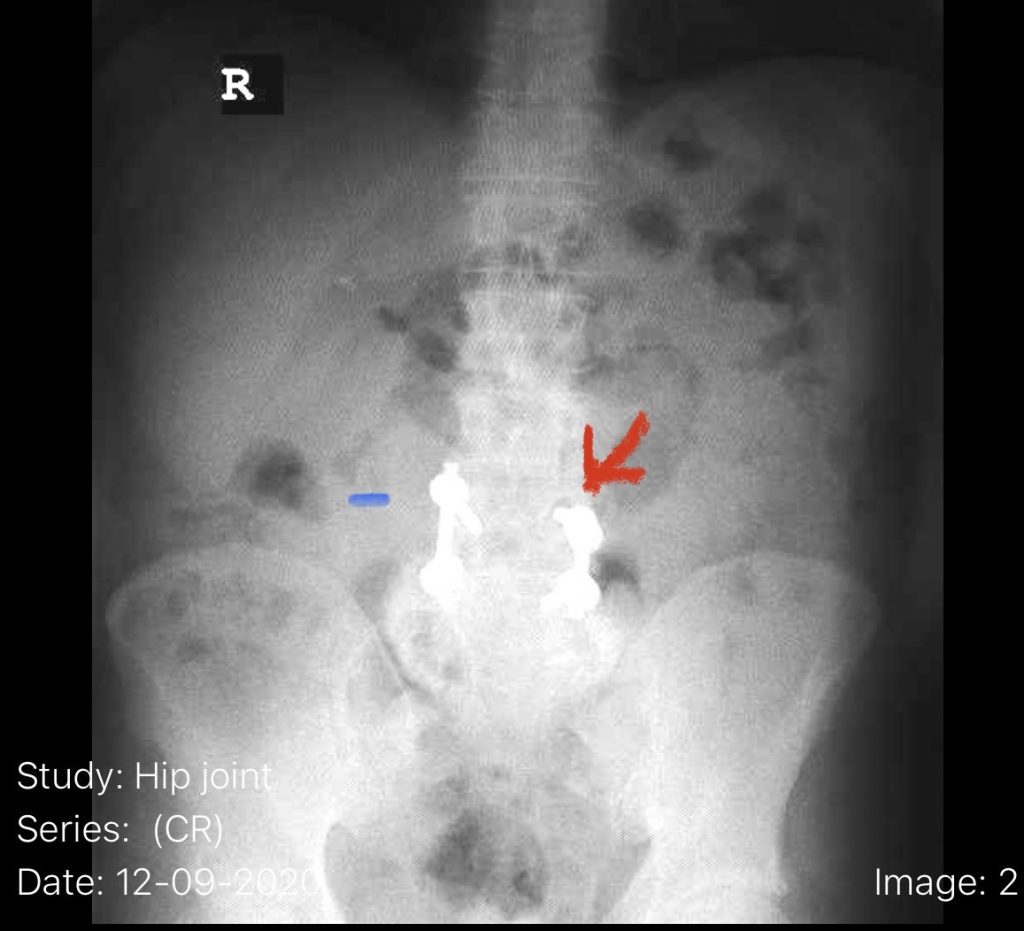

Fig 6: Plain AP x-ray demonstrating a lucency around the L4 screw (red arrow). Note the paucity of bone at the L4-5 level (blue dash) compared to below at L5.

The patient also had a retrolisthesis at L3-4 with mild stenosis. It was also noted that he had lucencies around the L4 screws, suggesting a pseudoarthrosis at L4-5. which is a lack of bony fusion (Fig 6). Patient was had failed conservative management and was taken to the operating room where his construct was explored. There was a complete lack of bony fusion mass between L4 and L5 and the screws were loose. Interestingly the L5-S1 region had a solid bony fusion where we had used BMP, but the L4-5 region did not. We removed the construct and removed the remnant of L4 lamina and the inferior processes and decompressed from L3 to to L5, decompressing well the L4 and L5 nerve roots. We placed new instrumentation from L3-5 with the use of BMP which was discussed with the patient prior to surgery (Fig 7). We also felt it was necessary because of the failure of the fusion. Post operatively the patient had an uneventful course with significant improvement of his prior symptoms.